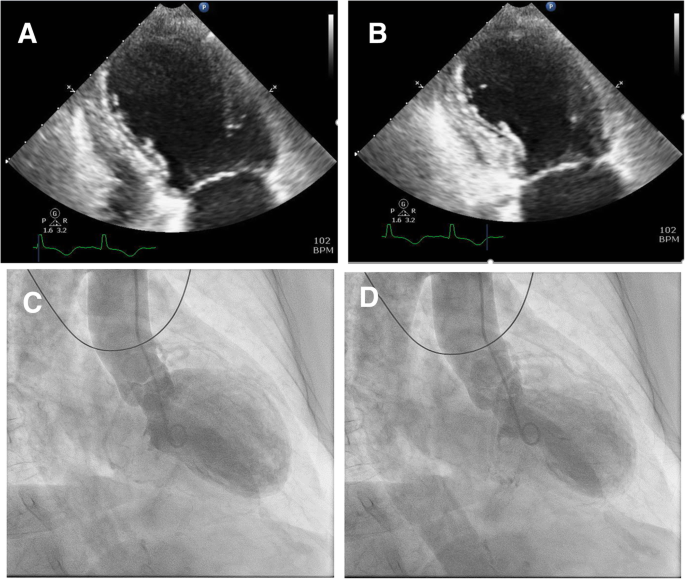

LV dysfunction is observed on imaging modalities like echocardiography and left ventriculography (Fig. 1). Three different types of contractile abnormality of the LV have been described. The most common pattern is apical akinesis with hyperkinesis of the basal segments. Other less common patterns include: combined akinesis of the mid-LV and apex, isolated akinesis of the mid-LV, and isolated basal akinesis [6]. Typically, LV ejection fraction (LVEF) is severely reduced, with median LVEF of 20%; interquartile range, 15 to 30% (normal LVEF range 55–75%) [2]. In a majority of patients, LVEF improves to greater than 50% on follow up. While cardiac recovery usually occurs in 4 to 6 weeks, it can take anywhere from 2.5 months to a year for a small proportion of individuals (~ 5%) [2, 7]. The prolonged duration required for normalization of LV systolic function predisposes individuals to the development thrombus in the LV with increased risk of embolization. Although uncommon, TCM can lead to complications like hemodynamic instability, atrial or ventricular arrhythmias, progressive heart failure, cardiogenic shock, and death. To aid in the diagnosis, “Mayo Clinic criteria” [8], can be used (Table 1).